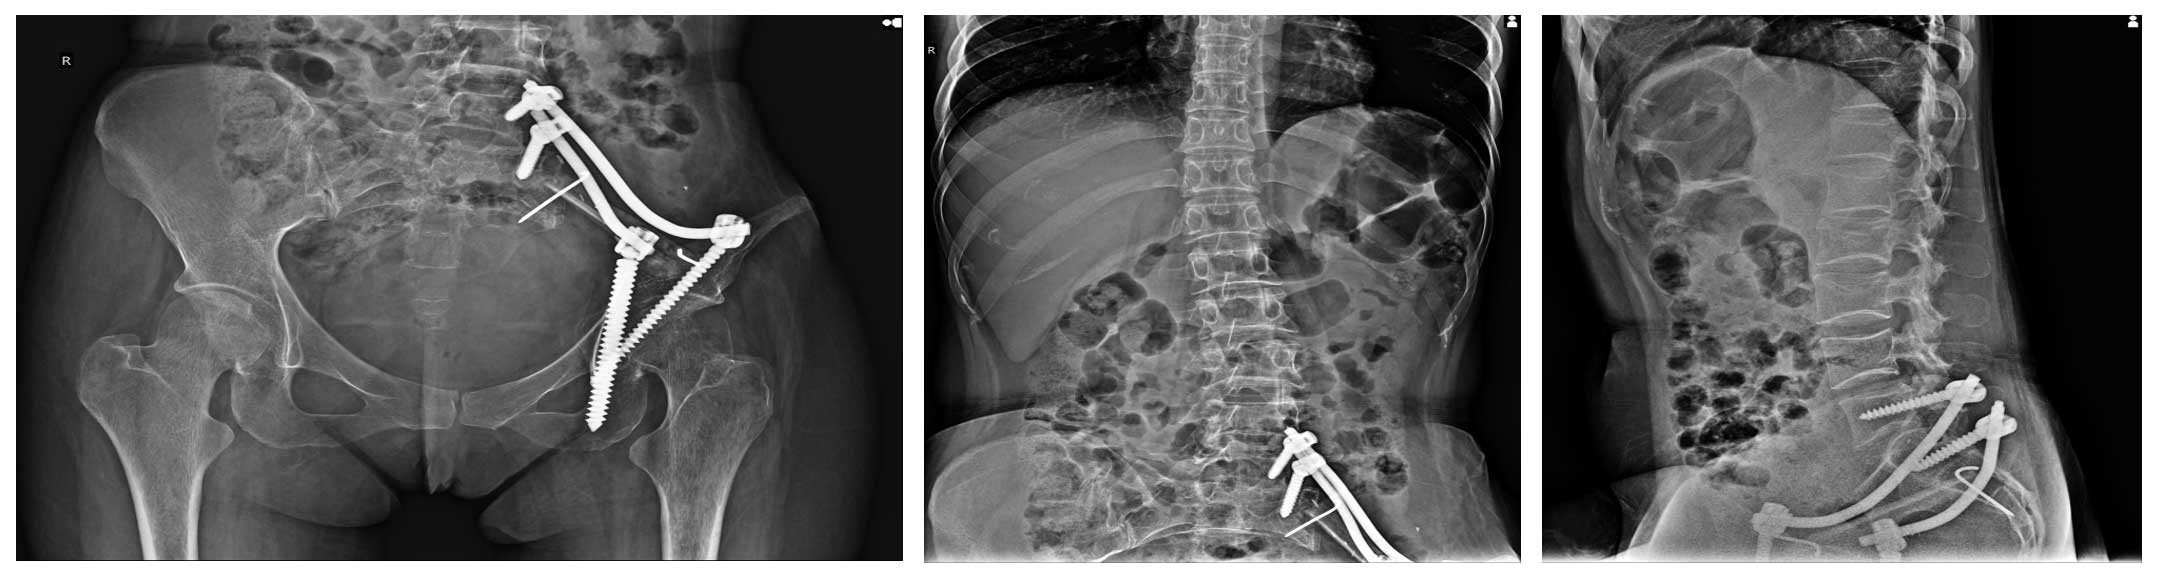

Ameliyat Öncesi: Röntgende ilk ameliyatta yapılan sakroiliak rezeksiyon ve rekonstrüksiyon, lomber vertebra kırıkları ve deformite görülmekte.

Ameliyat Sonrası: Röntgende parsiyel laminektomi+korpektomi sonrası yapılan çimentolama ve lumbopelvik fiksasyon görülmekte.